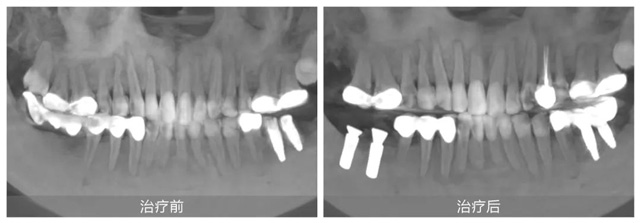

她自小牙齿不好,早年正牙过程中不幸遭遇正畸片切不当导致下颌右侧两颗磨牙严重受损,之后未经正规处理直接拔牙,造成重要磨牙缺失,严重影响咀嚼功能。随后原治疗机构采用倾斜智齿制作了不良烤瓷长桥修复,导致前磨牙牙髓坏死造成根尖炎。雪上加霜的是,五年前又被某口腔机构蹩脚医生把上颌两侧磨牙做了不必要的牙冠,之后下颌左侧两颗磨牙也因种植体位置不正导致牙冠频繁脱落,种植体也有折断风险。

果然,徐会医生不负所托轻松完成了刘女士下颌左侧的牙冠修复。并对其他牙齿问题提出了一套综合治疗方案:先拆除不良修复体,拔除下颌右侧的倾斜智齿,然后在缺牙处植入两颗种植牙,并对前磨牙实施根管治疗。这一方案更加微创,也更加经济和高效。